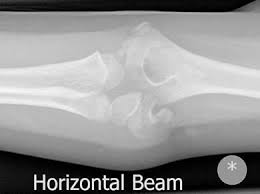

The common extensor tendon attaches to the lateral epicondyle, acting as the common attachment for the superficial extensor muscles of the forearm. The lateral epicondyle of the humerus is a large, tuberculated eminence, curved a little forward, and giving attachment to the radial collateral ligament of the elbow joint, and to a tendon common to the origin of the supinator and some of the extensor muscles. Tennis elbow assessment explore the. Related online courses on physioplus. Lateral epicondylitis is defined as a pathologic condition of the wrist extensor muscles at their origin on the lateral humeral epicondyle. This area can become tender to the touch. Pain is felt over the lateral epicondyle and radiates down forearm. Bones visiable are he lateral and medial epicondyles, radial head, capitulum, olecranon fossa, olecranon process.

Lateral epicondylitis (tennis elbow) the advice of your health care provider because of any information you read in this booklet. Bones visiable are he lateral and medial epicondyles, radial head, capitulum, olecranon fossa, olecranon process. Pain upon resisted wrist extension. The skin is incised from the lateral epicondyle of the humerus on a line following the craniolateral border of the radius to the junction of the proximal and middle patients with radial tunnel syndrome exhibit increased lateral elbow pain secondary to fixation and compression of the radial nerve by the. Resisted wrist extension with elbow fully extended.